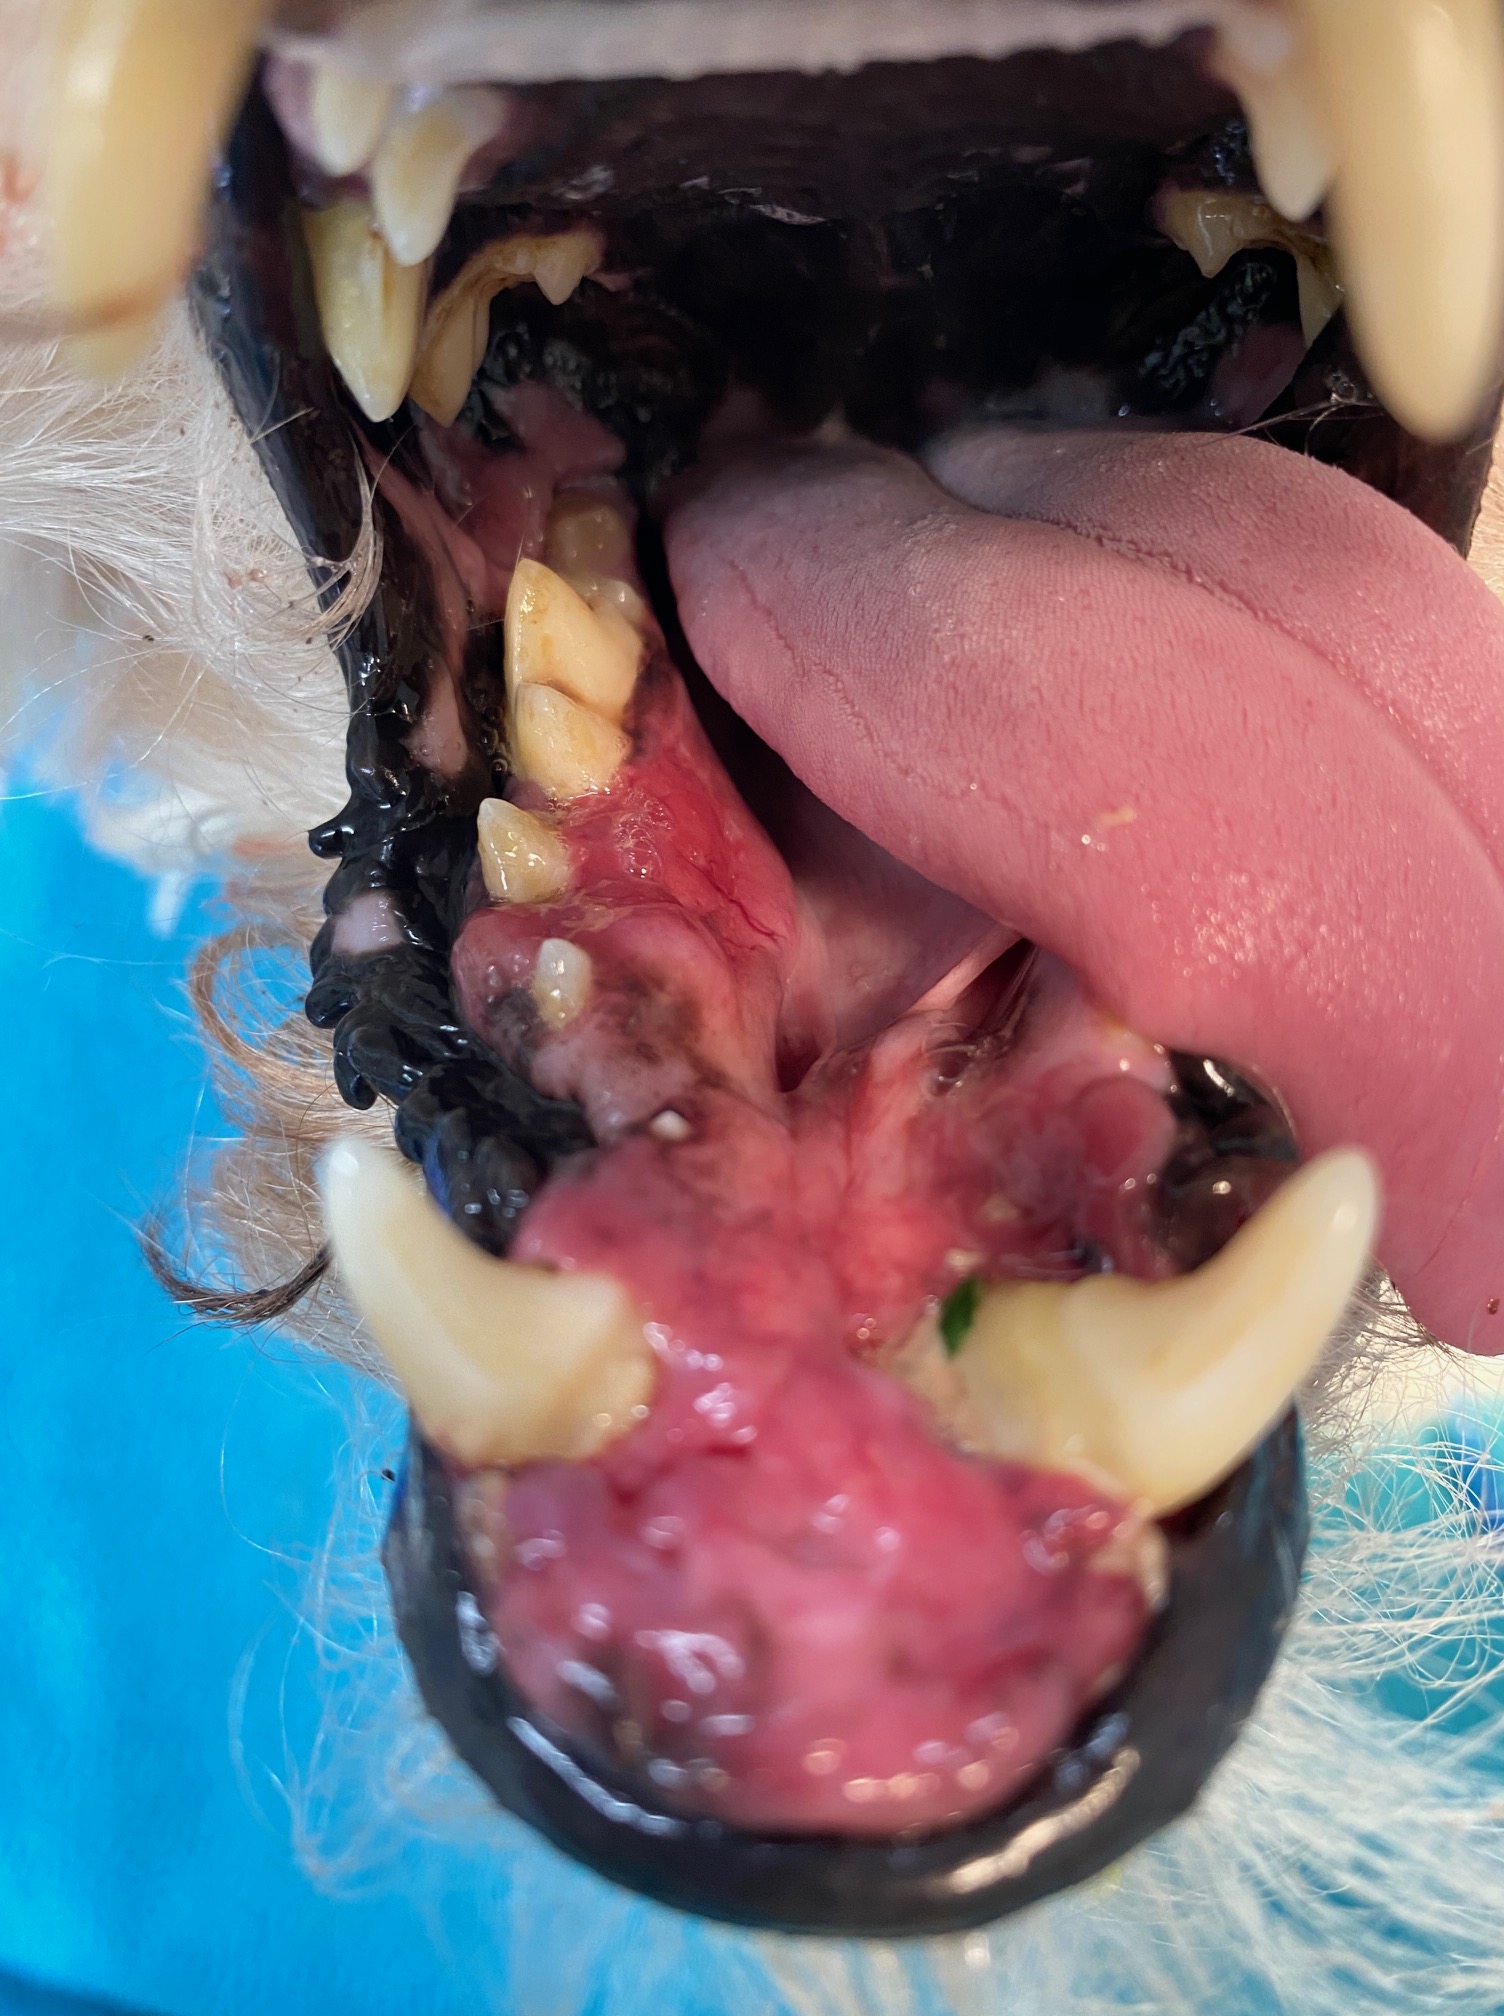

A large gingival flap was made and 203, 202, 201, 101, 102, 103, 104, 105 and 106 were extracted using a vet tome, elevators and luxators. The friable gingiva was resected just above the mucogingival margin. The buccal mucosa was bluntly dissected the sutured to the palatal mucosa. 304, 404 and 405 were extracted using the vet tome. The owner was warned pre-operation of the complication of jaw fractured. This did not occur as I used the vet tome, burred away some alveolar bone, used gentle elevation and was patient!. The gingiva between the canines, where the lower incisors had been previously extracted, was also friable. I placed cruciate sutures over the canine sockets to hold the blood clot in place but could not suture the gingiva closed as the tissue was too friable and inflamed. The area between the lower canines was left to heal by secondary intention.

The photos at the bottom of this blog show the same view before and after surgery.